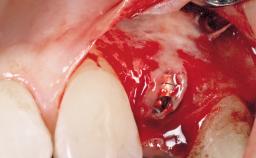

Late Placement of an Implant in a Maxillary Left Central Incisor Site

A 30-year-old female patient had lost tooth 21 and was referred to our clinic for consultation and treatment. Due to advanced apical infection, tooth 21 had been extracted two months earlier at another clinic and an acrylic-resin tooth had been bonded to the adjacent teeth. The patient desired implant treatment to avoid any damage to the adjacent natural teeth. While the patient had no history of any systemic disorder, she was a heavy smoker and exhibited medium to advanced periodontitis in the entire jaw. After the initial treatment to achieve a pocket probing depth of less than 4 mm and no bleeding on probing, a decrease in the height of the papillae mesial and distal to the extraction site and overall gingival recession were observed.

| Soft Tissue Grafting | Simultaneous |